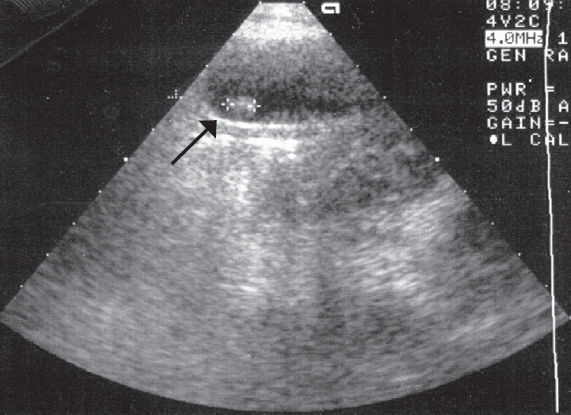

Возраст пациентов был от 2 до 17 лет. В 70,4 % случаев заболевание отмечено у девочек, соответственно у мальчиков — 29,6 %. У 7,8 % пациентов заболевание возникло на фоне гемолитической анемии. Около трети пациентов предъявляли жалобы на умеренно выраженный болевой синдром или чувство тяжести в верхней половине живота. У 15 % детей клинические симптомы возникали на фоне погрешностей в диете. При этом клинические и биохимические показатели анализов крови и мочи, в том числе печеночного профиля, были в пределах нормы. Вышеуказанные симптомы послужили показанием к проведению ультразвукового исследования (УЗИ). У пациентов с бессимптомным течением ЖКБ УЗИ было назначено по другому поводу. При проведении УЗИ у всех пациентов в желчном пузыре обнаруживали гиперэхогенные образования (рис. 1), смещаемые при изменении положения тела (конкременты).

Рис. 1. Ультразвуковая картина конкремента в желчном пузыре

Fig. 1. Ultrasonic pattern of concretion in the gallbladder